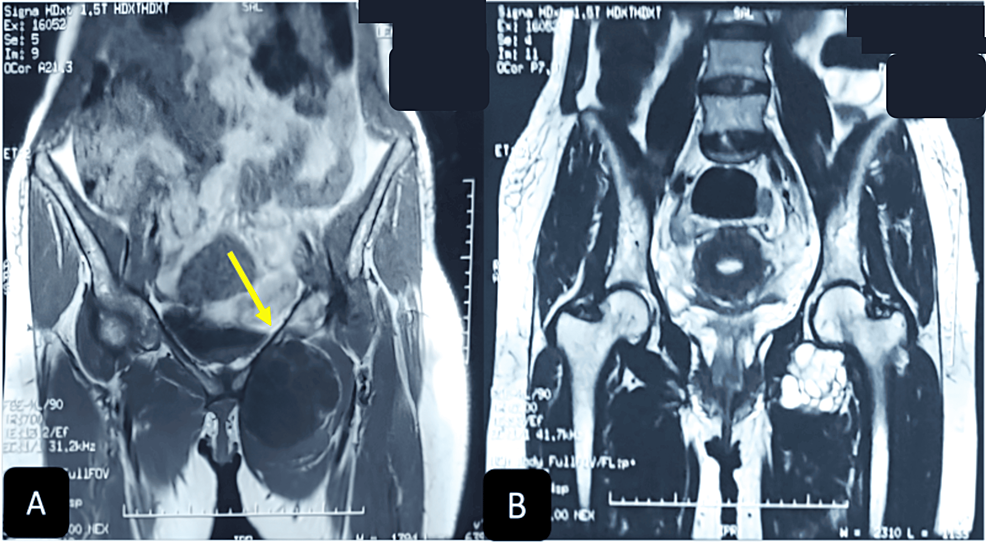

From www.cureus.com

Cureus Hydatid Cyst of the Inguinal Region An Exceptional Localization Pectineus Injection Pectineus is a short quadrangular muscle extending from the pubis to the area just below the lesser trochanter of femur. It has the most superior attachment of all the thigh. The goal of the interfascial injection technique for blocking the obturator nerve is to inject local anesthetic solution into the interfascial space. The pectineus muscle assists in hip adduction and. Pectineus Injection.